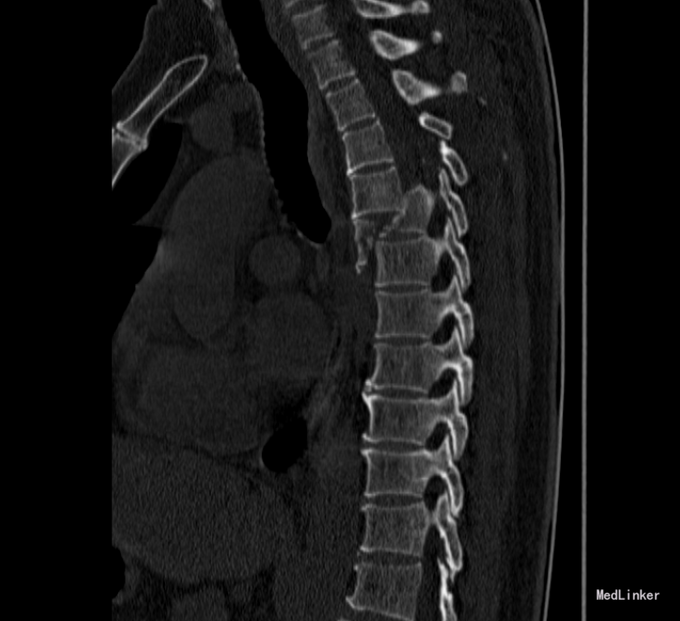

患者于2014-08-13日11:30左右骑摩托车摔倒,伤后一过性意识不清,清醒后感觉胸部疼痛,双下肢活动受限,急诊送至盘锦市宽甸县中心医院,行胸CT、头CT、胸椎三维CT,提示为胸椎骨折,急诊行面部伤口清创缝合,具体治疗不详。患者及家属为求系统治疗,急来我院,急诊予以行辅助检查,提示:胸椎骨折;急诊以“多发外伤”为主诊断收入我科.

诊断:胸3-6椎体骨折,胸髓损伤,双下肢全瘫。 入院后完善检查,查无手术禁忌症后行胸椎骨折后路切开复位椎板减压椎弓根钉内固定术